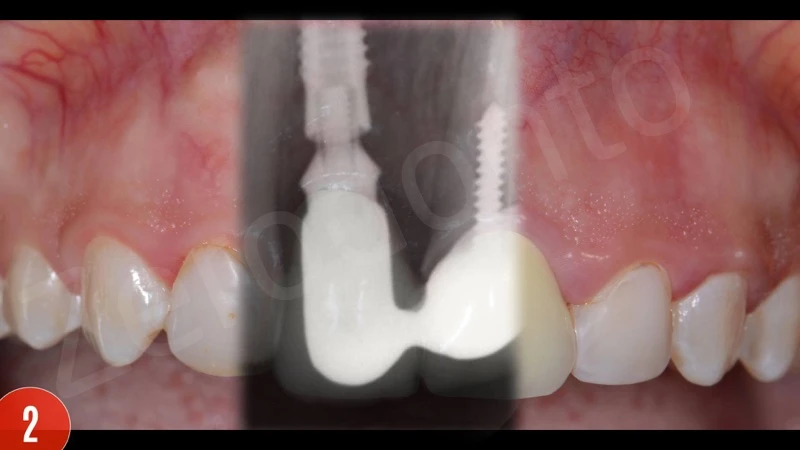

Sau khi đánh giá X-quang ban đầu, các thành phần phục hình của cấy ghép implant đã không phù hợp, răng giả được nối liền. Ngoài ra, vị trí cấy ghép quá sâu. Chảy máu khi thăm khám dương tính.

Sau khi gây tê tại chỗ, răng giả đã được cắt và loại bỏ. Sau đó, xương ổ răng vẫn hiện diện quanh implantl. Trong lần điều trị này, điều chỉnh chính xác abutment được thực hiện và xác nhận với X-quang. Khu vực cấy implant được để lành thương mô mềm. Sau 8 tuần lành thương mô mềm, phẫu thuật ghép mô liên kết (CTG) đã được lên kế hoạch với vạt bao, vạt nhú lợi xoay xiên (oblique rotated papilla flap) bằng cách sử dụng các đường rạch dưới lợi viền. Kĩ thuật chia tách tạo khả năng di động thích hợp cho vạt niêm mạc. Các phần lợi viền phía cổ được loại bỏ. CTG được lấy bằng kỹ thuật loại bỏ biểu mô. Để bù đắp thiếu hụt niêm mạc, CTG được gấp đôi và khâu bằng với vật liệu tự tiêu trước khi khâu cố định. CTG đã được cố định mặt môi, ôm lấy bề mặt abutment. Vạt niêm mạc tự do, thụ động, căng được khâu.